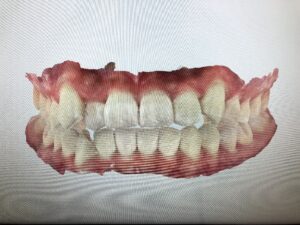

おまけにiTeroの優秀な機能「プログレスアセスメント」を紹介します。

治療計画上の歯並びと、iTeroで撮影した実際の歯並びを比較して、

歯一本一本が計画通りに動いているのか分析してくれる機能です。

緑の部分は順調に動いていて、グレーや黄、紫の部分は動きがイマイチなようです。

自分が思っていた以上にカラフルになってショックです、、、。